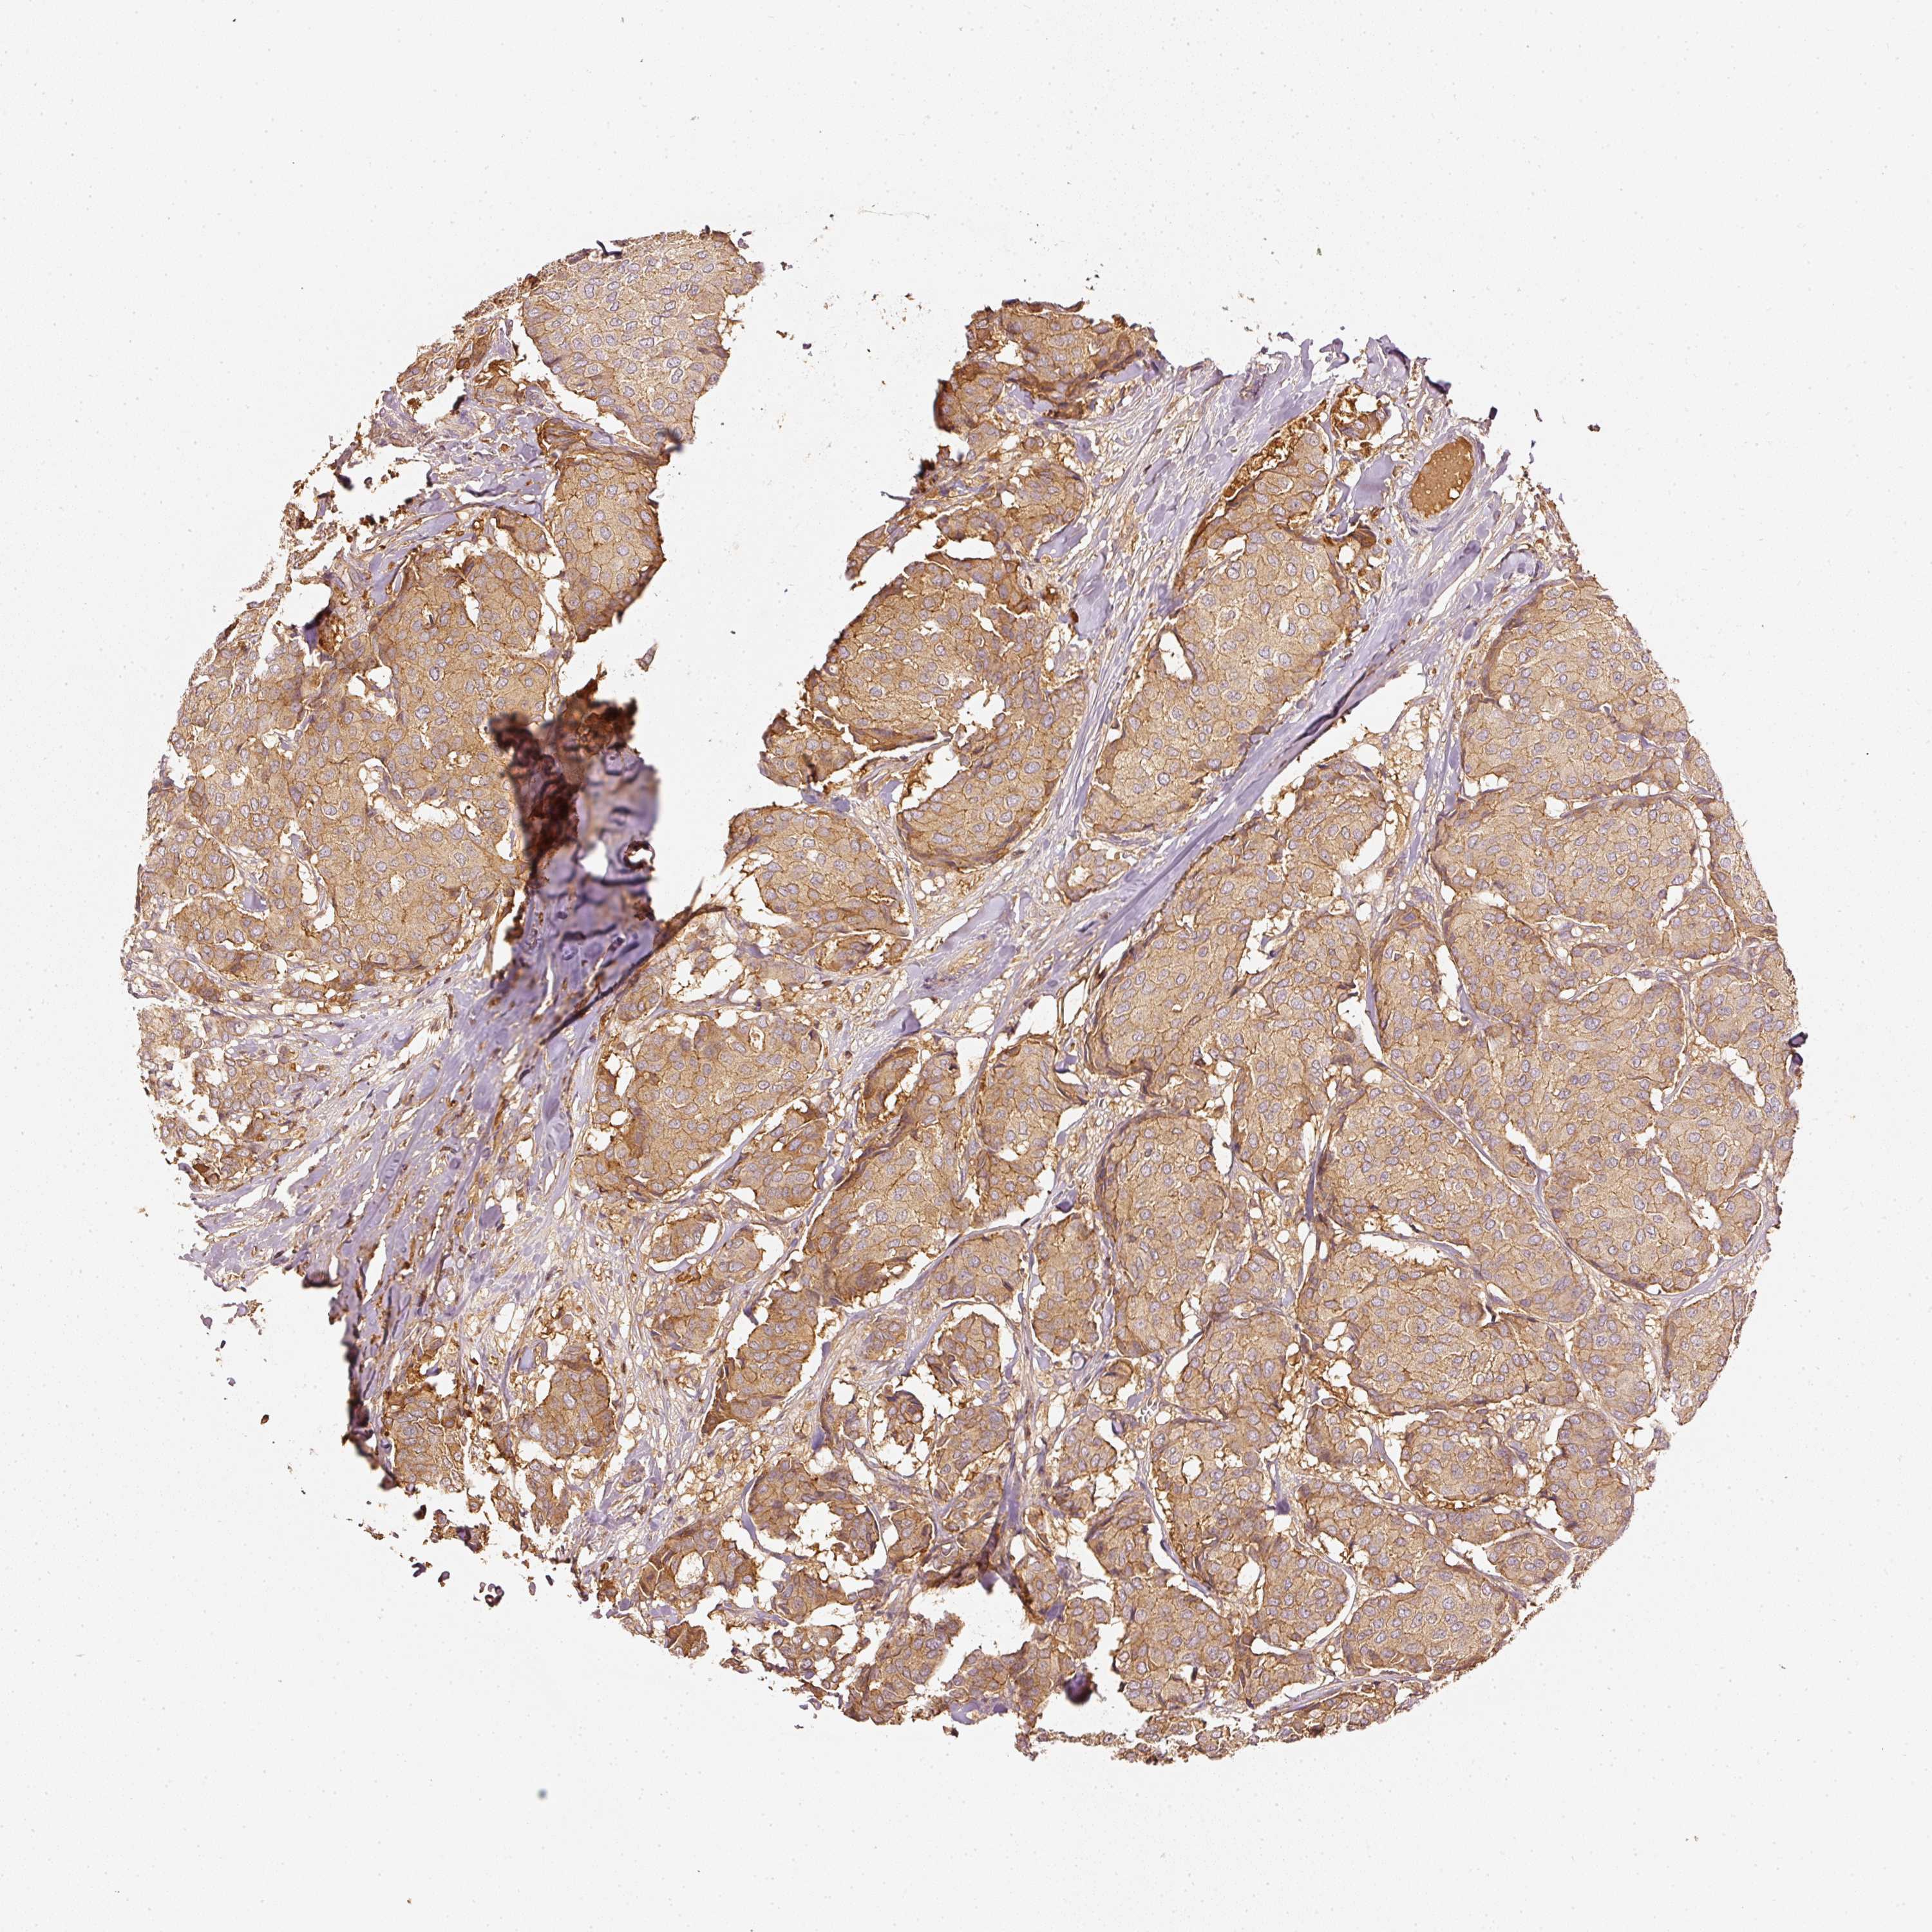

CANCER BREAST CANCER Show tissue menu

BRCA TCGA BRCA VALIDATION PROTEIN EXPRESSION

ANTIBODIES

AND

VALIDATION